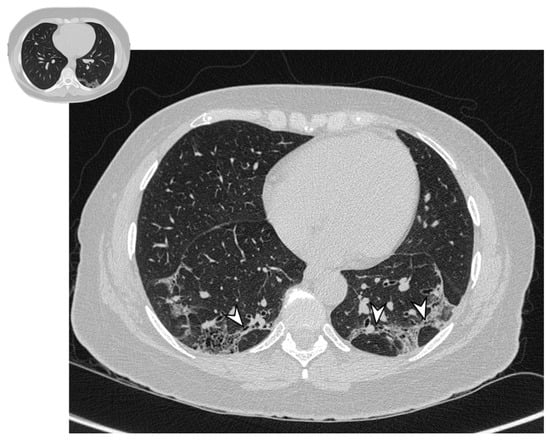

Of all four atoll signs, only one has been observed at follow-up HRCTs (Figure 13, Table 8).

Figure 13. Presence of atoll signs (white arrowheads) in a patient with COP, which were still recognizable despite steroid therapy.